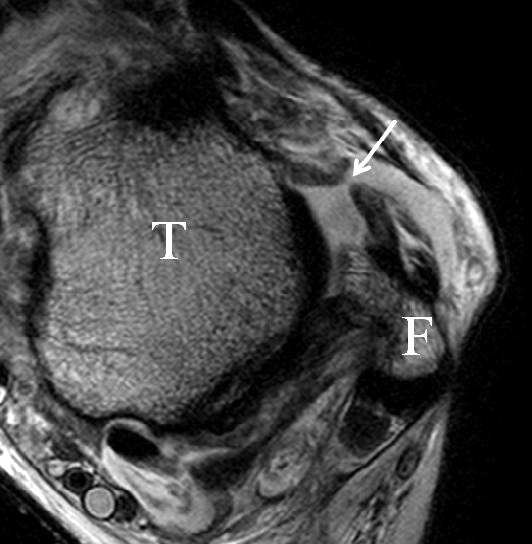

Die Kombination aus 3 Tesla Hochfeldtechnik und/oder Verwendung hochauflösender Spulen (Empfangseinheiten des Signals) erhöht die Signalausbeute. Dies erlaubt mit akzeptablen Messzeiten (3-4 Minuten pro Sequenz) im Routinebetrieb eine Darstellung mit einer Schichtdicke von 1-2 mm und einer Ortsauflösung von 0,2 x 0,2 mm in der Schichtebene in den anatomisch am besten zeichnenden 2D Turbospinechosequenzen. Der Unterschied der diagnostischen Wertigkeit zwischen einer kernspintomographischen „Standarduntersuchung“ und einer HR-MRT wird besonders in der chondralen Diagnostik sichtbar (Abb. 1 a-c). Unter Verwendung von 3D Sequenzen, die jedoch entscheidende Schwächen bei der Darstellung der Ligamente aufweisen, werden sogar Schichtdicken weit im Submillimeterbreich erreicht. Eine weitere Erörterung der Sequenz spezifischen Eigenheiten soll jedoch an dieser Stelle unterbleiben.

Das Ligamentum fibulotalare anterius entspricht einer bifaszikulären Struktur (Abb. 2 a) mit interponierendem fibrovaskulärem Gewebe (S. K. Sarrafian (ed). 2003). Es gibt jedoch Variationen der Ligamentanatomie. In 55% liegt das LFTA als bifaszikuläres Band (Abb. 2 a), in 9% als monofaszikuläre Bandstruktur (Abb. 2 b) und in 36% als multifaszikuläre, striäre Variante (Abb. 2 c) vor 3.

Das LFTA verbindet die antero-inferiore Fibulaspitze mit dem Processus lateralis tali und inseriert hier an einem oder zwei kleinen Tuberkeln 3. Der in Neutralposition horizontale Verlauf erleichtert die kernspintomographische Darstellung in dieser Standardebene. Das LFTA weist durchschnittlich eine Breite von knapp über 2 mm auf 4. Somit sind bei einer Routinedarstellung in 3 mm Schichtdicke Anschnittsphänomene, die die Diagnostik erschweren, regelmäßig anzutreffen. Dementsprechend sind auch die ligamentären Subfaszikel nicht zu differenzieren. In koronarer Darstellung ist dies aufgrund der hohen Auflösung in der Schichtebene jedoch möglich (Abb. 2 a-c), wobei hier wiederum eine Integritätsbeurteilung des Bandes erschwert ist. Unter Verwendung hochauflösender Techniken im Millimeterbereich (Schichtdicke) sind hingegen auch in der axialen Ebene die subfaszikulären Strukturen zu beurteilen (Abb. 3).